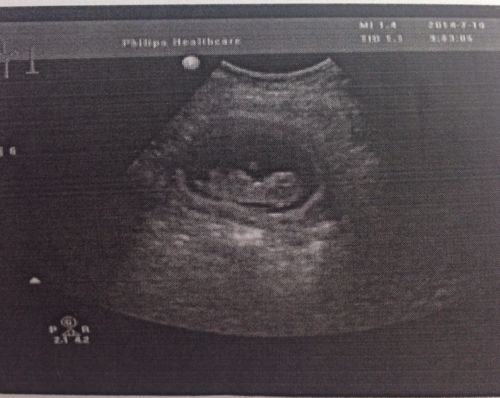

怀孕三个月看不出男孩女孩吗?昨天刚做的闭超.成熟都'i了,还看不见吗?

三个月胎儿

胎儿三个月图片

怀孕三个月胎儿彩超

三个月胎儿真实图片

怀孕三个月的胎儿图像

三个月胎儿图彩超图片

三个月怀孕成型图片